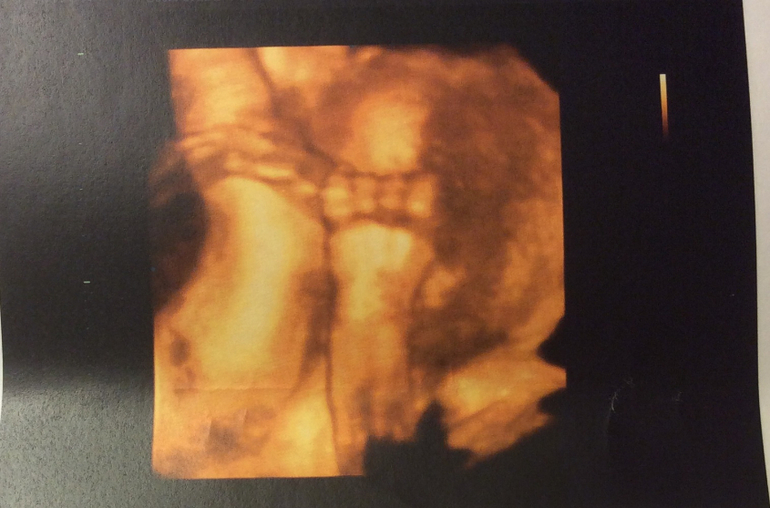

По последним 3d узи, которые я делала в Москве, все хорошо с малышкой. Только сидела пока на попе. или вообще поперек, вытянув ножки, как на шезлонге) потом фото приложу. Ножки мои по фото, все говорят. А вот носик пока кажется картошечкой) но может просто личико маленькое. Главное - что здорова вроде! надеюсь, за 2 недели перевернется.

P.S. Прикреплю и дочины фото на память. Буду вспоминать, как она там ножку на ногу лежала с вытянутыми ножками, как за пуповину держалась ручкой, как -будто в трамвае за перекладину)